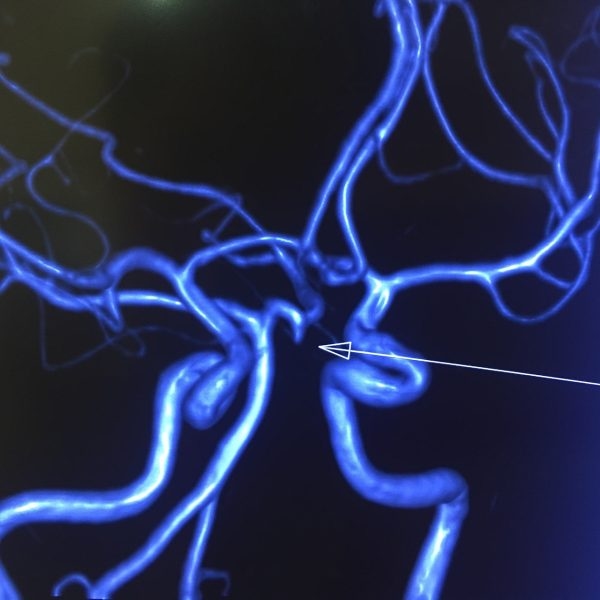

– Chụp mạch máu não: giúp phát hiện những bất thường ở mạch máu não như dị dạng mạch máu não, huyết khối trong mạch máu não, xuất huyết dưới nhện, xuất huyết não ở thùy não, ….

Chụp cộng hưởng từ (MRI) mạch máu não phát hiện nút phình động mạch não.